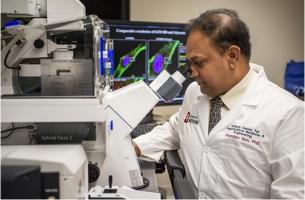

BRULÛRES, GRANDES PLAIES : Une bio-imprimante de peau au chevet du patient